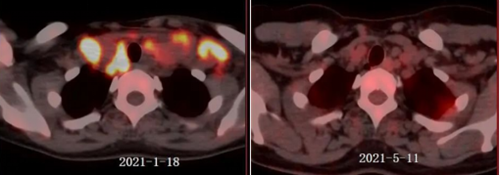

双侧锁上下窝区可见多肿大淋巴结,代谢明显增,4周期化疗明显缩小,代谢明显降低,提示部分缓解(Deauville评分:3分)